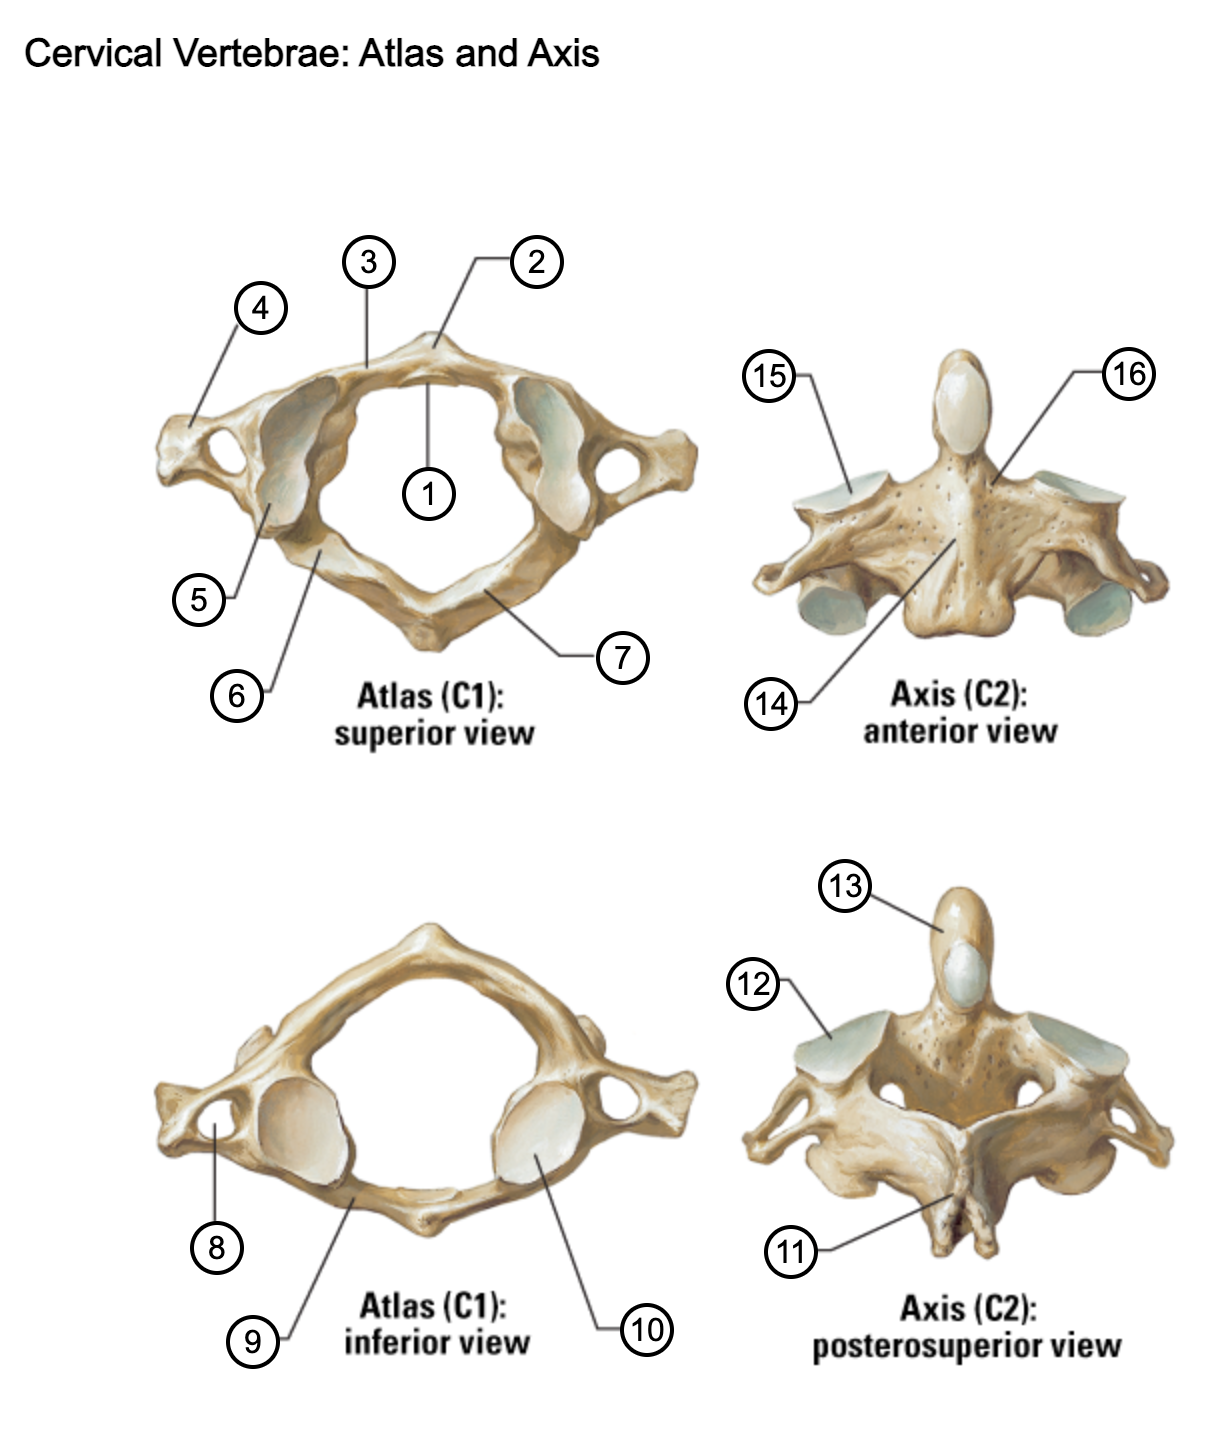

1

facet for dens

2

anterior tubercle

3

anterior arch

4

transverse process

5

superior articular surface of atlas

6

groove for vertebral artery

7

posterior arch

8

transverse foramen

9

anterior arch

10

inferior articular surface of atlas

11

spinous process

12

superior articular facet

13

dens of axis

14

body of axis

15

superior articular facet for atlas

16

pedicle of vertebral arch